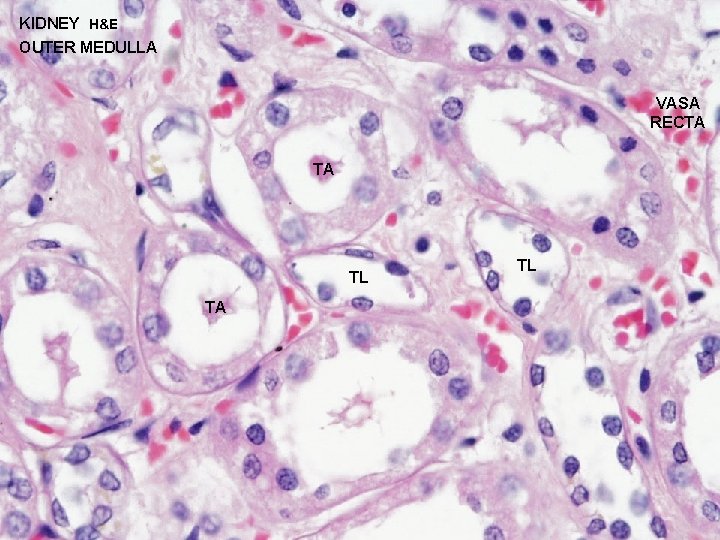

URINARY SYSTEM THE NEPHRON & COLLECTING DUCTS MEDULLA: OUTER ZONE 1 - STRAIGHT PORTIONS OF PROXIMAL TUBULE (THICK DESCENDING) 2 - STRAIGHT PORTIONS OF DISTAL TUBULE (THICK ASCENDING) 3 - THIN SEGMENTS OF LOOP OF HENLE (DESCENDING & 4 -ASCENDING) COLLECTING DUCTS INNER ZONE 1 - THIN SEGMENTS OF LOOP OF HENLE (DESCENDING & 2 -ASCENDING) COLLECTING DUCTS

URINARY SYSTEM THE NEPHRON & COLLECTING DUCTS MEDULLA: OUTER ZONE 1 - STRAIGHT PORTIONS OF PROXIMAL TUBULE (THICK DESCENDING) 2 - STRAIGHT PORTIONS OF DISTAL TUBULE (THICK ASCENDING) 3 - THIN SEGMENTS OF LOOP OF HENLE (DESCENDING & 4 -ASCENDING) COLLECTING DUCTS INNER ZONE 1 - THIN SEGMENTS OF LOOP OF HENLE (DESCENDING & 2 -ASCENDING) COLLECTING DUCTS

KIDNEY H&E OUTER MEDULLA C TA D C D TD TL

KIDNEY H&E OUTER MEDULLA VASA RECTA TA TL